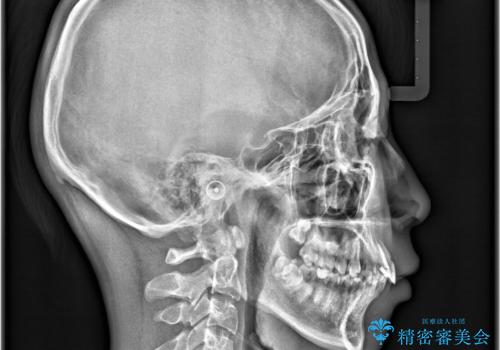

- 「歯のでこぼこを治したい 1年くらいで矯正を終わらせたい」を主訴に来院された患者様です。

叢生量は多く無く歯の傾斜も標準傾斜だったので歯は抜かずにワイヤー矯正で治療を行いました。

左側は2級傾向が強く臼歯の遠心移動をご提案しましたが、1年以内に矯正を終わらせたいという患者様のご意向で希望されず叢生を改善する矯正となりました。